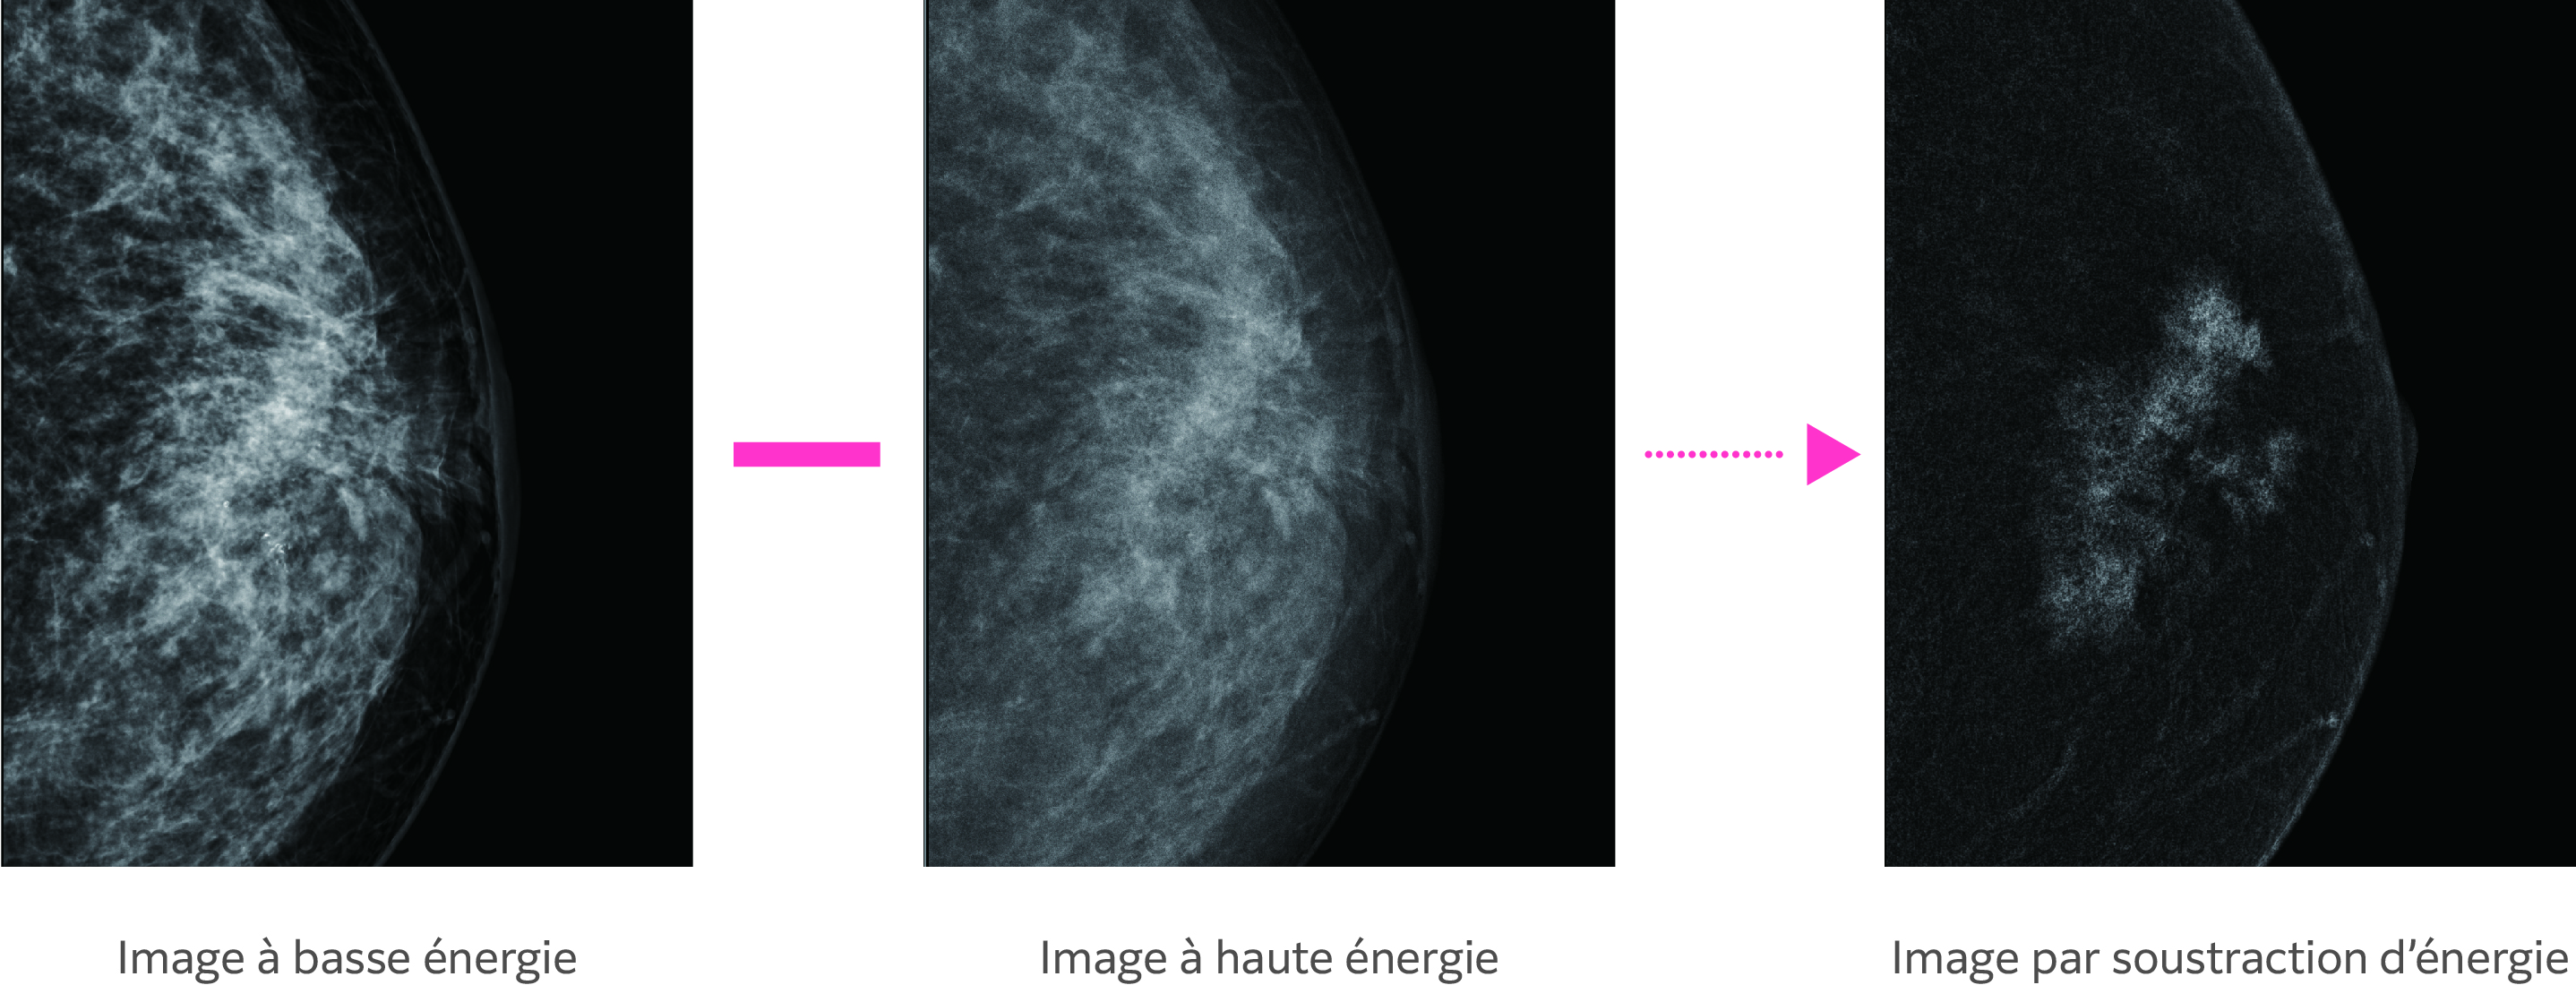

Acquisition en continu d’une image à basse tension (basse énergie) proche de la mammographie conventionnelle et d’une image à haute tension (haute énergie) avec un filtre Cu, dans une même compresssion. Le logiciel génère une image de soustraction d’énergie automatiquement.

*Lorsqu'un produit de contraste iodé est utilisé.